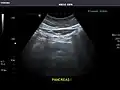

Pancreas: Visualized portions unremarkable.

Pancreas -